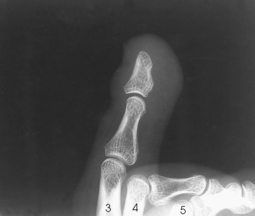

Structures shown: Images show a lateral projection of the phalanges of the toe and the IP articulations projected free of the other toes (Figs. 6-29 to 6-33).

Structures shown: The resulting image shows a true lateral projection of the lower third of the tibia and fibula; the ankle joint; and the tarsals, including the base of the fifth metatarsal (Figs. 6-94 and 6-95).

Fig. 6-94 Bones shown on lateral ankle. Including base of fifth metatarsal on lateral ankle projection can identify Jones fracture if present.